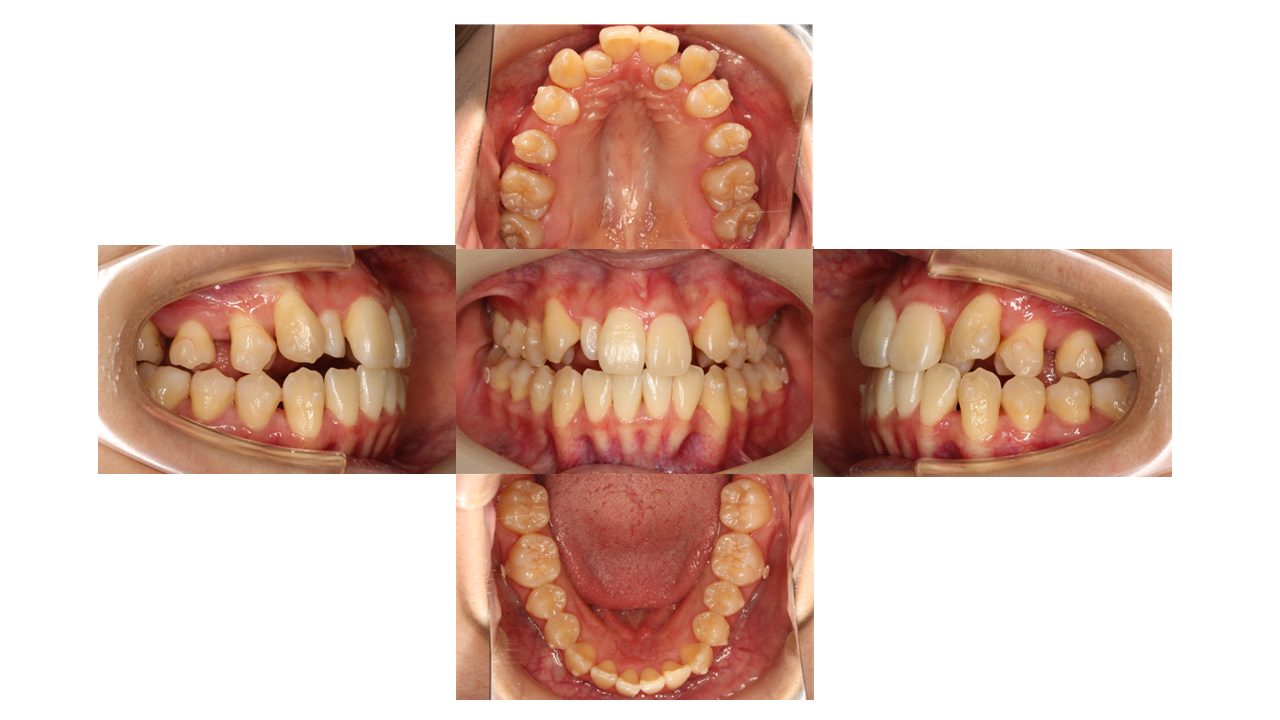

1年経過の口腔内の状態です。

奥歯を後ろに動かし、前歯を並べるスペースを作っていきます。